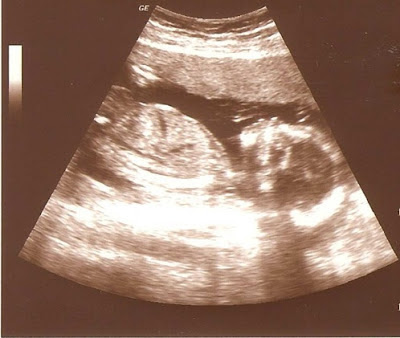

Das Geschlecht verschweige ich weiterhin, aber eine Pofilaufnahme möchte ich schon herzeigen - weil es ein zu schönes Bild ist. Ich hoffe, man kann es gut erkennen...

| 19 + 3 |